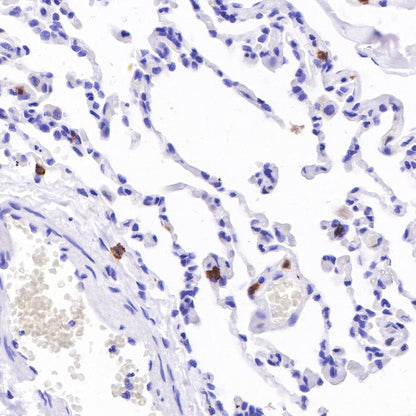

IHC shows positive staining in paraffin-embedded human gastric cancer. Anti-CD103 antibody was used at 1/100 dilution, followed by a HRP Polymer for Mouse & Rabbit IgG (ready to use). Counterstained with hematoxylin. Heat mediated antigen retrieval with Tris/EDTA buffer pH9.0 was performed before commencing with IHC staining protocol.